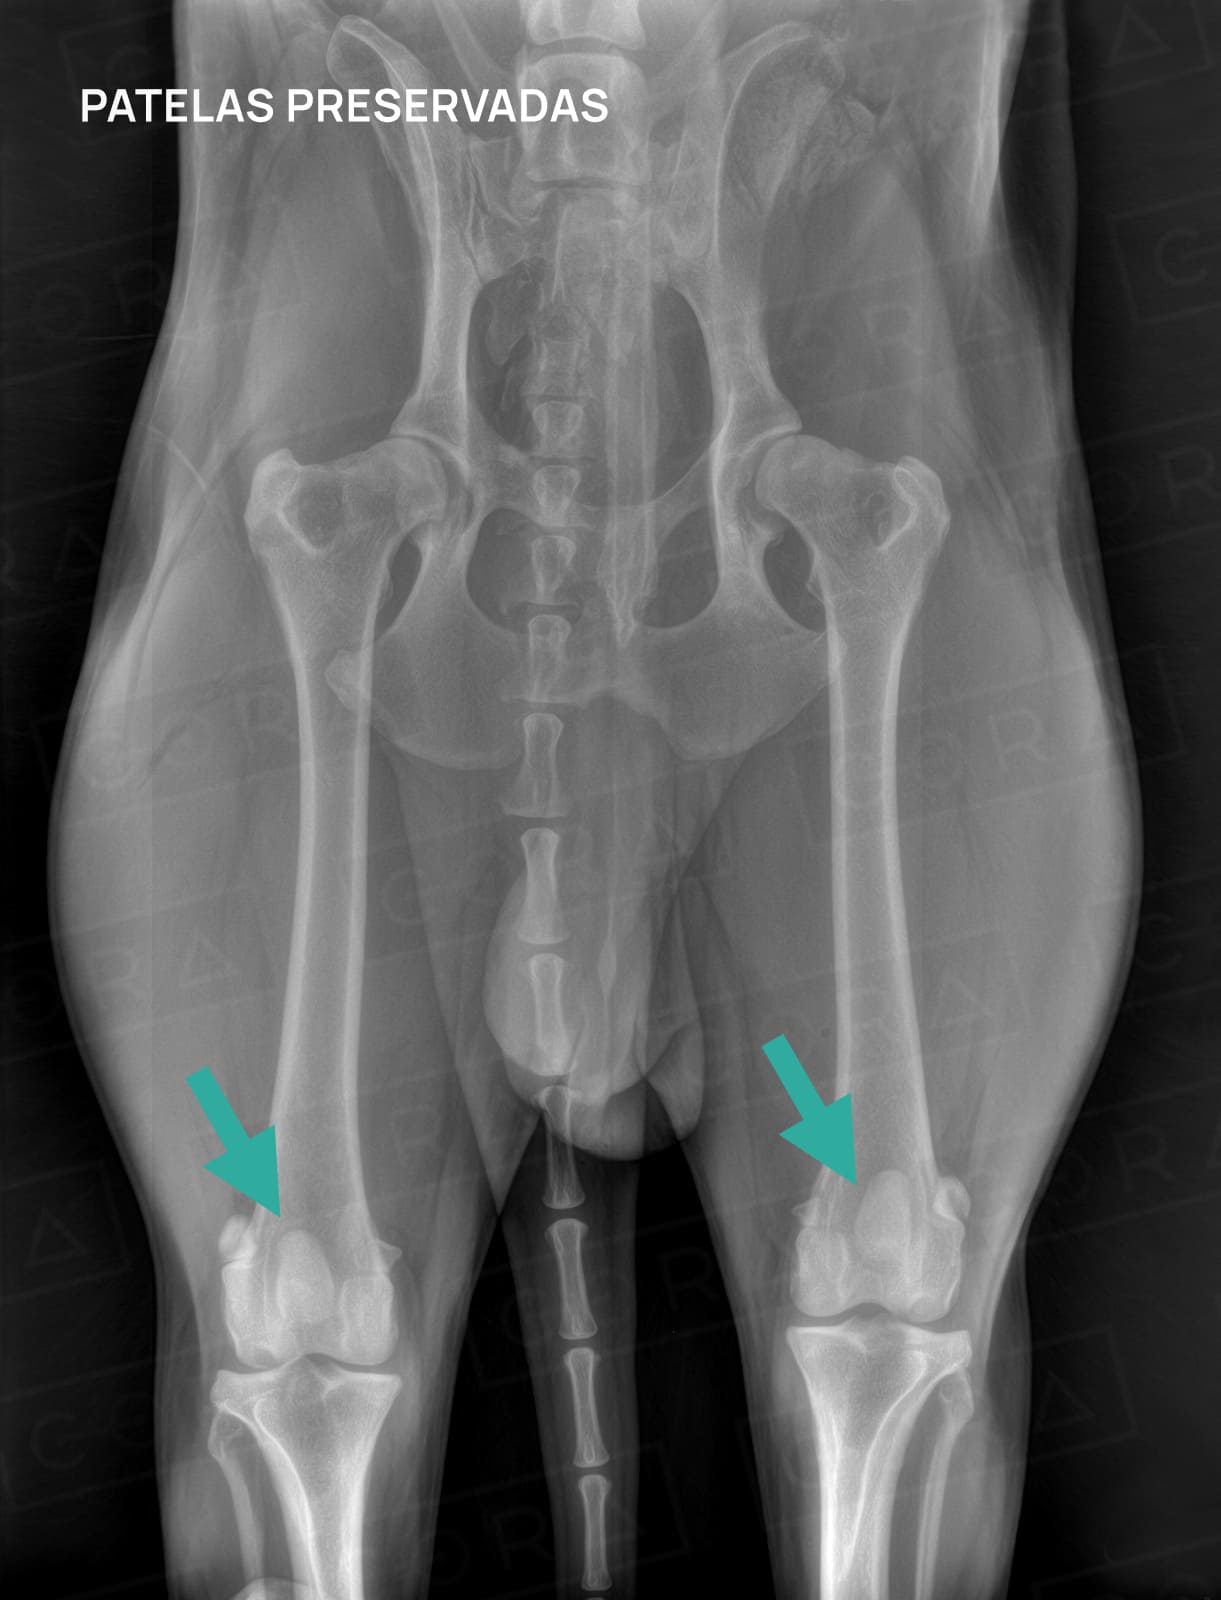

O diagnóstico é baseado no exame físico, radiográfico e, algumas vezes, até a tomografia com reconstrução anatômica é necessária para o estudo e compreensão das deformidades anatômicas presentes no membro do animal.